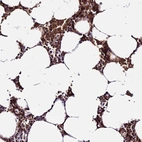

Immunohistochemical staining of human bone marrow shows strong cytoplasmic positivity in hematopoietic cells.